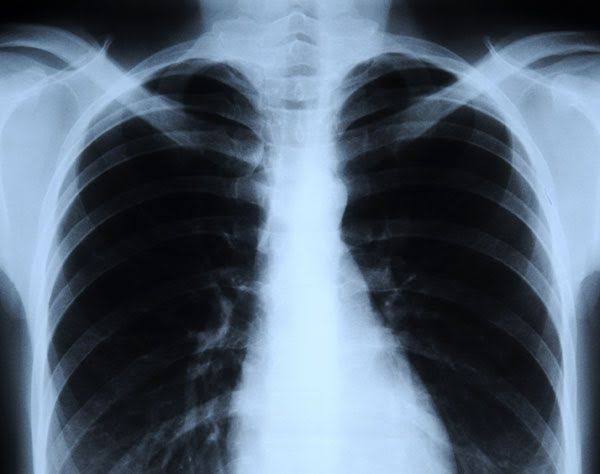

X Ray

As the name implies, this is the examination of the inner body especially the bones and joints. It can also be used to detect problems affecting soft tissue, such as internal organs. The speculation that X-rays cause infertility in female is absolutely false. This is because the radiation in routine scans is too low to cause female infertility. X-rays can also be used to detect tumors, diagnose pneumonia ( Chest X-rays) etc.